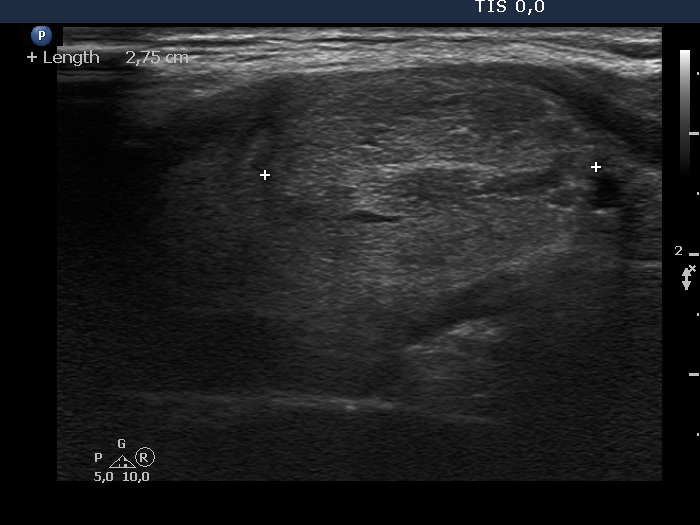

Ethanol sclerotherapy: non-toxic solid nodules - Case 5

Fourteen years after the therapy (ultrasonographic picture 2)

Right lobe, longitudinal scan.